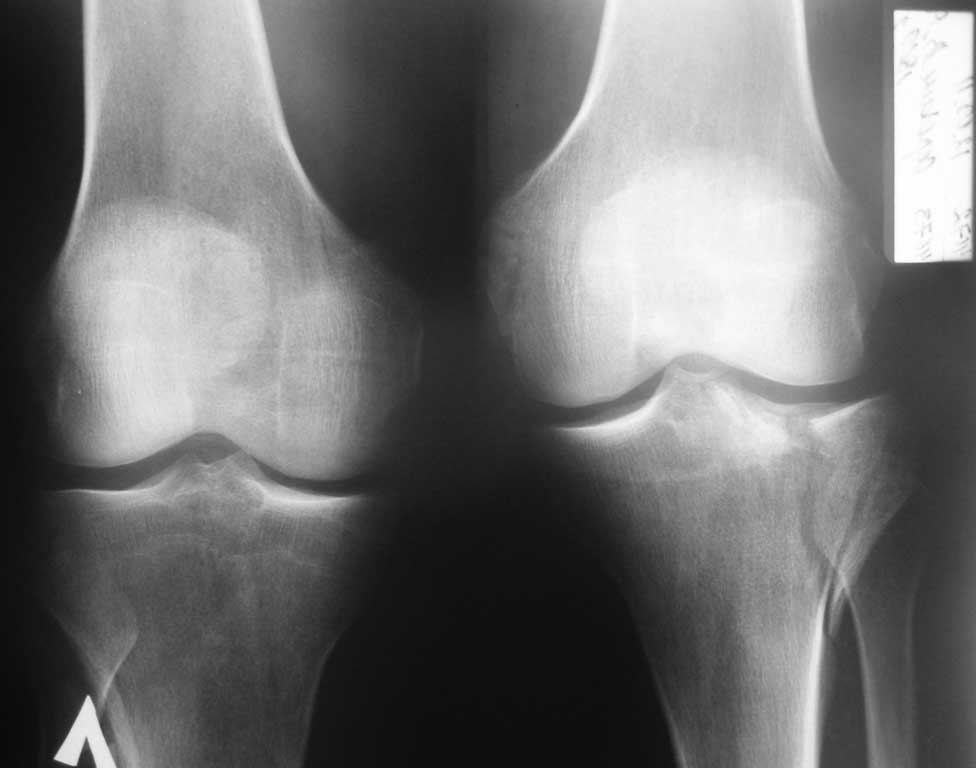

Здравствуйте уважаемые коллеги! Хотелось бы услышать Ваше мнение о том как помочь пациенту с

данным переломом, в условиях отсутствия артроскопии и "Т" и "L"-образных пластин. Травма в

результате ДТП, 41 год, пост геморрагическая анемия, перелом тибиального плато, В1.

Имеются в наличии только спонгиозные шурупы ( смешно конечно и горько). Хотелось бы

уточнить, стоит ли делать артротомию для репозиции, или попытаться закрыто фиксировать

перелом?